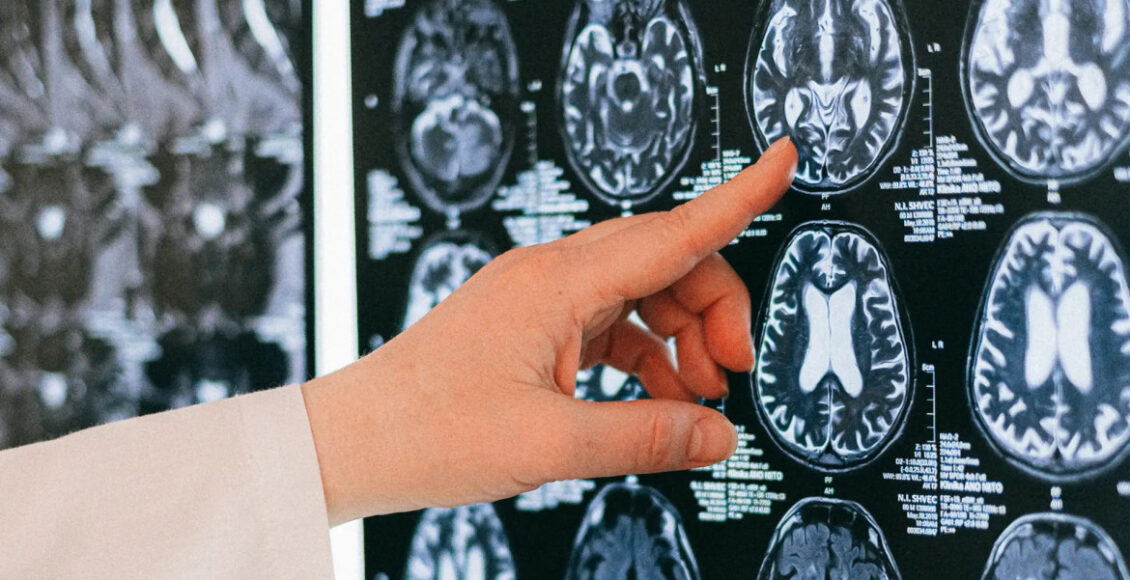

Muchas veces los médicos no pueden determinar dónde se originó el tumor, por lo que elegir el tratamiento adecuado se convierte en un verdadero acertijo.

El cáncer de origen primario desconocido (CUP) o cáncer de origen primario oculto se da cuando se encuentra cáncer en una o más localizaciones metastásicas, pero el lugar primario no puede ser determinado. Esto ocurre en una pequeña porción de cánceres.

Esta falta de datos en lo que respecta al origen dificulta el tratamiento, ya que los médicos no pueden dar a los pacientes medicamentos de “precisión”, los cuales suelen estar aprobados para tipos de cáncer específicos.

Para darle aún más validez a las predicciones del modelo, los expertos compararon los datos sobre el tiempo de supervivencia de los pacientes con CUP con el pronóstico típico para el tipo de cáncer que predijo el modelo.

Así fue como descubrieron que los pacientes con CUP, en los que la tecnología predijo que tendrían cáncer con un mal pronóstico, como el cáncer de páncreas, mostraron tiempos de supervivencia más cortos. Mientras tanto, los pacientes con CUP que se predijo que tendrían cánceres con mejores pronósticos, como los tumores neuroendocrinos, tuvieron tiempos de supervivencia más prolongados.

Además, se puso atención en los tipos de tratamientos que habían recibido los pacientes con CUP analizados en el estudio. Alrededor del 10% de estos pacientes habían recibido un tratamiento dirigido, según la mejor suposición de sus oncólogos sobre dónde se había originado su cáncer. Entre esos pacientes, aquellos que recibieron un tratamiento consistente con el tipo de cáncer que el modelo predijo para ellos obtuvieron mejores resultados que los pacientes que recibieron un tratamiento típicamente dado para un tipo de cáncer diferente al que el modelo predijo para ellos.